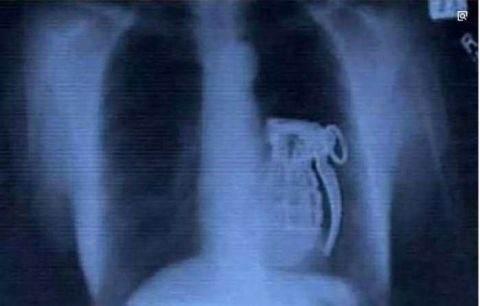

​↓这个是奇葩吞个手榴弹!

看X光下那些意外进入身体的异物!个个奇葩搞笑